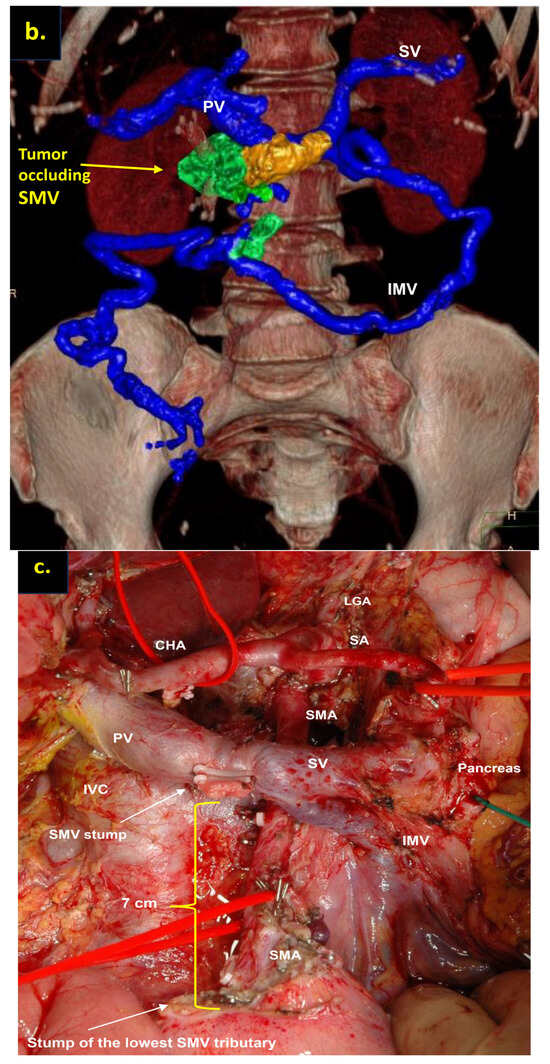

Pancreatoduodenectomy with the SMV and all its tributaries resection without reconstruction for the uncinate PDAC in 57-year-old female. On CT the tumor invades the SMV, which is occluded, the SMV-SV confluence is preserved, and the IMV collaterals are well-developed with dilated large collecting intestinal vein, without right-sided vein collaterals and varices. (a) Three-dimensional MIP and (b) three-dimensional VR reconstructions show the dilated large collecting intestinal vein flowing into the IMV, which connects to the SV; (c) the picture of the operating field after the extended Whipple procedure with the SMV and all its tributaries resection without reconstruction. CHA—common hepatic, LGA—left gastric, SA—splenic, SMA—superior mesenteric arteries, IVC—inferior vena cava; (d) the way of the intestinal blood flow after surgery.

In this study, only cases with full excision of SMV trunk and resection of all its tributaries, namely middle and right colic veins, ileocolic trunk, and all the first-order SMV branches (jejunal and ileal), without the reconstruction of above-mentioned vessels, were included. The usual length of the resected SMV with the branches in these cases was 7–8 cm (Figure 5 and Figure 7).

We used different post-processing CT techniques for the assessment of the peripancreatic vessels and collateral venous blood flow adequacy, such as shaded surface display, maximum intensity projection, and 3D volume-rendered (VR) reconstruction imaging. Now, when planning SMV resection with excision of all its tributaries for “low” pancreatic cancer, we consider CT-based 3D-VR reconstruction the best and most necessary option for the depiction of the collateral venous system. Compared to the other rendering CT techniques, VR is superior in delineating vessels, pancreatic parenchyma, the tumor, and adjacent structures (Figure 1a–d, Figure 5a,b, Figure 6a,b and Figure 7a,b,d) [43,44,45].